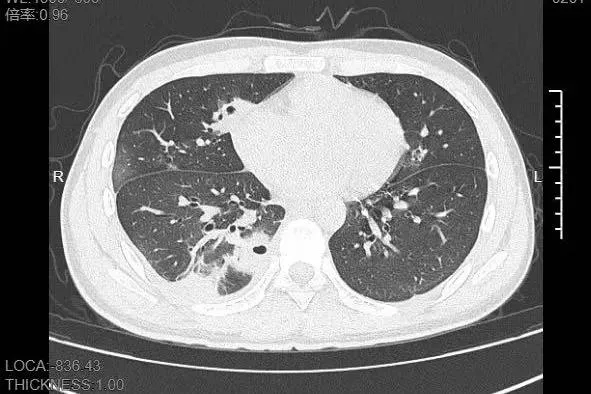

熬到第三天,小林已经烧到 39℃,赶紧来到宁波大学附属第一医院就诊。接诊的呼吸与危重症医学科丁群力主任医师一看他的症状,立刻安排了 CT 检查。结果显示:小林的肺里有十几个空洞,部分肺组织已经坏死,这是典型的血源性肺脓肿。